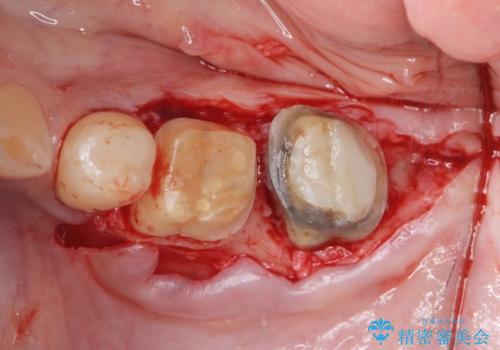

- 著しい歯ぎしりですり減ってしまった、奥歯のクラウンのやりかえを希望され来院されました。

このままの状態でクラウンのやりかえを行うと高さが低く安定の悪いクラウンとなってしまうため、事前に歯周外科手術を行い歯ぐきを下げることで安定性の高いクラウンを製作する治療計画としました。